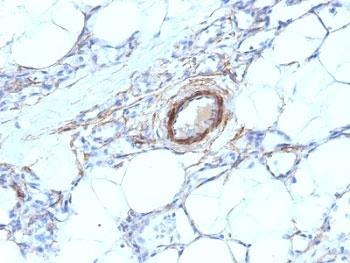

IHC: Formalin-fixed, paraffin-embedded human breast carcinoma stained with SMMHC antibody (MYH11/923).